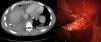

La figura 1 muestra la tomografía axial computarizada de exostosis costal solitaria en el quinto arco costal con crecimiento intratorácico, hemotórax e imagen videotoracoscópica de la lesión ósea de borde incisivo antes de su resección.

Figura 1

El osteocondroma o exostosis costal es el tumor óseo benigno más frecuente a nivel torácico. Con frecuencia presenta un crecimiento intratorácico que puede causar una laceración pulmonar y hemotórax1 tras sufrir traumatismo torácico cerrado, como el caso de la imagen clínica. La videotoracoscopia2 derecha permitió una perfecta visualización de la tumoración ósea, su extirpación y la evacuación del hemotórax producido.